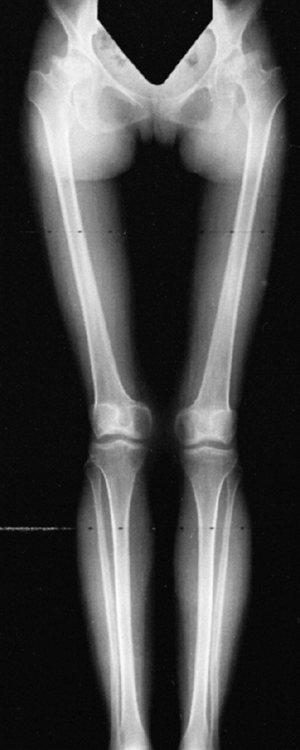

knee valgus is usually relatively symmetric. It results partially from

uneven growth of the proximal tibial epiphysis, with the lateral side

being underdeveloped (Fig. 8.14). An exostosis

may arise medially from the proximal tibial metaphy-sis. The acetabulae

have spike formations at the medial and lateral edges. The capital

![]() |

|

Figure 8.14

Lower extremities of a 5-year-old child with chondroectodermal dysplasia, demonstrating the characteristic pronounced hypoplasia of the lateral proximal tibial epiphysis with marked genu valgus. |